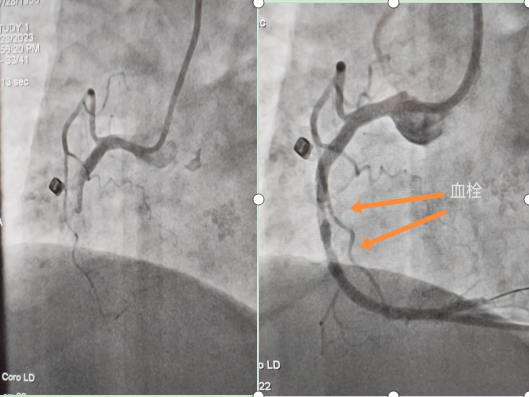

血管的硬化狹窄非一日形成,任何治療手段都不會讓血管恢復原本的狀態(tài)。心臟支架手術(shù)也不是一種根治的辦法,它只是通過物理的方法來達到緩解癥狀的目的。且無論手術(shù)與否,患者均需要長期服用藥物,在手術(shù)過程中及術(shù)后,還可能會發(fā)生多種并發(fā)癥。在插入導管和植入支架時,可能會導致血管壁損傷,引發(fā)出血或血腫。在置入支架后,血管壁可能會再次狹窄(支架內(nèi)再狹窄),導致血流受阻,在手術(shù)或術(shù)后的幾天內(nèi),血管內(nèi)可能形成血栓,這種情況需要抗凝治療或抗血小板藥物來預防或治療血栓形成。既然術(shù)后還是需要長期服藥,那為什么還會在臨床上廣泛的應用呢?